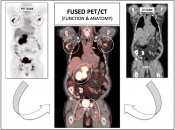

A PET/CT scan is a hybrid imaging study that combines a PET scan’s ability to demonstrate metabolic activity (“a functional exam”) with the CT scan’s ability to define precise anatomic detail (an anatomic exam).

While PET/CT imaging is useful in a number of clinical settings, including cardiac and dementia imaging, its most common use (and the use for which PETCTMD was created) is in the field of Oncology. [Fig. 1]  [Fig. 2]

Fused Images: The impressive power of PET/CT is dramatically illustrated when we fuse the “anatomic” CT images with the “functional” PET images, revealing an elegant anatomic map of all active disease.